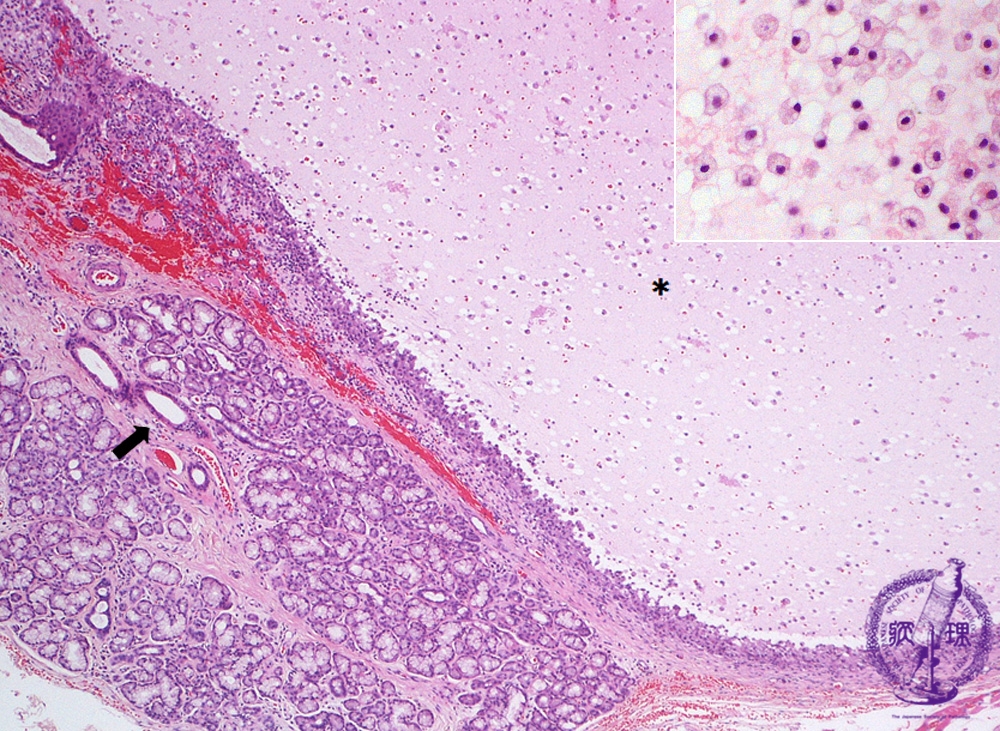

Microscopic finding (HE stain, low-power view) : Adjacent to the minor salivary gland (*), a cyst containing mucoid material and mucophages (mucous laden macrophages) has formed within the granulation tissue (upper right). Ductal dilatation is observed within the salivary gland (arrow).